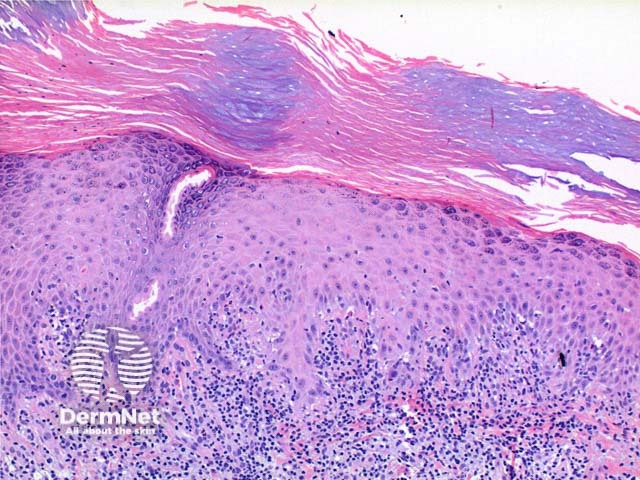

Scanning power view of porokeratosis reveals a hyperkeratotic lesion with a discrete parakeratotic column at the margin, or two if the whole lesion is represented (Figure 1). The diagnostic feature is the presence of a cornoid lamella which represents the clinically visible raised margin of the lesion. The cornoid lamella is a parakeratotic column overlying a small vertical zone of dyskeratotic and vacuolated cells within the epidermis (Figures 2 and 3). There is also a focal loss of the granular layer. A mild lymphocytic infiltrate may be seen around an increased number of capillaries in the underlying dermis.

Porokeratosis of Mibelli: This prototypical lesion may demonstrate a depression in the epidermis beneath the cornoid lamella.